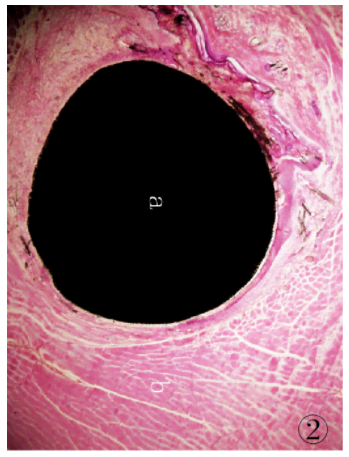

1.3.9 組織切片的染色將組織切磨片經(jīng)蒸餾水充分清洗后,參照文獻[5]的方法進行染色:蘇木精染液30 min,自來水充分沖洗,1%鹽酸乙醇分化30s,流水沖洗后再入溫水返藍(lán),置伊紅染液5min,自來水沖洗,待組織切片自然干燥后經(jīng)Technovit 7210VLC封片,光鏡下觀察。制得的組織切片經(jīng)HE 染色后,細(xì)胞核、細(xì)胞質(zhì)著色對比鮮明,組織細(xì)胞形態(tài)清晰,可直接在光學(xué)顯微鏡下進行組織學(xué)觀察,可見植入的CF/PEEK 復(fù)合材料與周邊肌肉組織結(jié)合緊密( 圖2、3) ,植入的復(fù)合材料周圍可見新生纖維結(jié)締組織,纖維囊壁結(jié)構(gòu)已形成。

圖2 低倍鏡下埋置有CF/PEEK 復(fù)合材料的肌肉組織病理切片:a.試驗樣品CF /PEEK復(fù)合材料; b. 肌肉組織